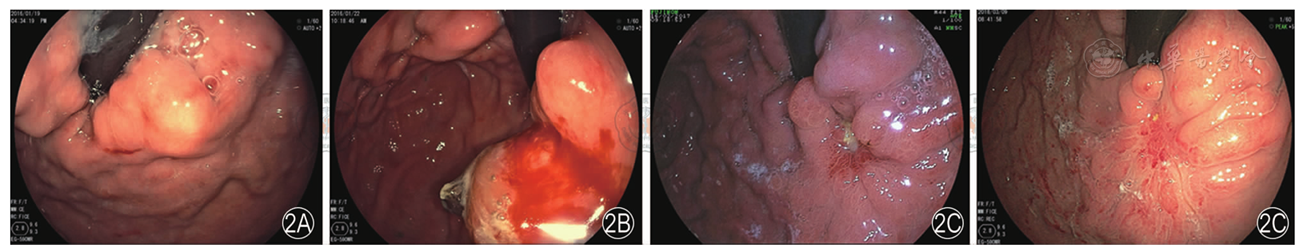

图2 胃静脉曲张黏合剂治疗后慢性排胶过程